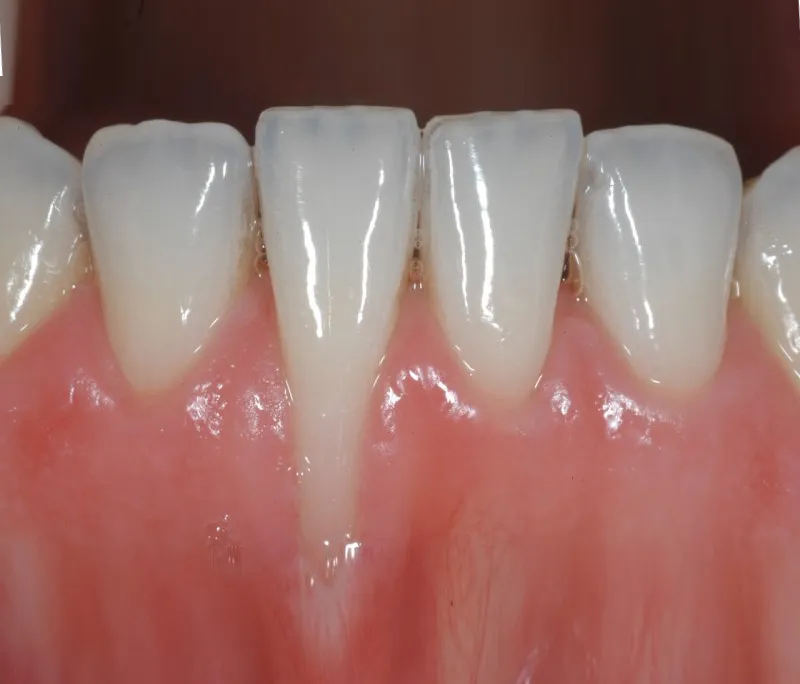

Vấn đề tụt lợi không chỉ gây ê buốt, khó chịu mà còn ảnh hưởng đến thẩm mỹ nụ cười. Bạn đang có ý định ...